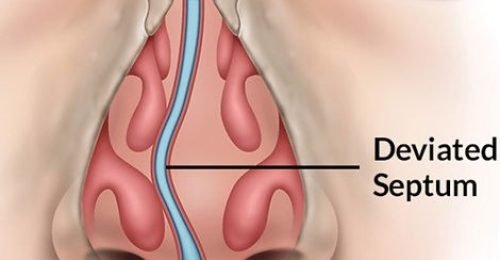

Do you often struggle with nasal congestion, difficulty breathing through your nose, or frequent sinus infections? A deviated nasal septum might be the root cause. At my ENT clinic in Delhi, I specialize in Septoplasty, a safe and effective surgical procedure to correct a deviated septum and restore natural breathing.

Septoplasty is a surgical procedure performed to straighten the nasal septum—the thin wall of cartilage and bone that divides the two nasal passages. When the septum is crooked or off-center, it can block airflow, leading to nasal obstruction, snoring, sinus infections, and even headaches.

Septoplasty corrects this deviation, allowing for improved airflow, reduced sinus pressure, and overall better nasal function.

With over 10 years of experience as an ENT surgeon in Delhi, I have performed numerous successful septoplasty procedures with a focus on patient comfort, safety, and long-term results. Every case is evaluated with advanced diagnostic tools, and treatment is tailored to each patient’s unique anatomy and symptoms.

Whether performed alone or alongside other procedures like turbinate reduction or FESS, septoplasty can offer lasting relief and significantly enhance your daily breathing and wellbeing.

If you’re tired of nasal congestion and poor airflow affecting your quality of life, Septoplasty may be the solution. Book an appointment today at our Delhi clinic to get expert evaluation and treatment options that are right for you.